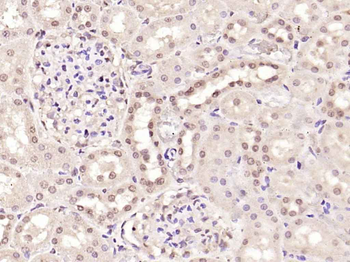

100 μl, 200 μl, 50 μlPhospho-Smad3 (Ser213) Rabbit Polyclonal Antibody [orb106193]

FC, IF, IHC-Fr, IHC-P

Bovine, Equine, Gallus, Guinea pig, Rabbit, Sheep

Human, Mouse, Rat

Rabbit

Polyclonal

Unconjugated

50 μl, 100 μl, 200 μl